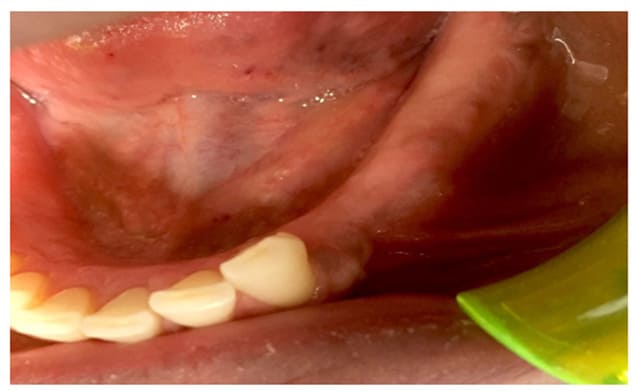

In Case 2, the patient exhibited favorable aesthetic results without neurological consequences. The post-operative CBCT at the 3-year follow-up indicated maintenance of the alveolar structure, with partial ossification of the defect.

Figure 8: Exposition of the lesion after the flap elevation

Figure 9: Follow up at 3 months